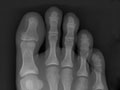

While X-rays of feet and hands are sometimes useful in the late stages of gout, X-rays aren't usually helpful in the early diagnosis. Pain often causes people to seek medical care before any long-term changes can be seen on an X-ray. But X-rays may help to rule out other causes of arthritis.